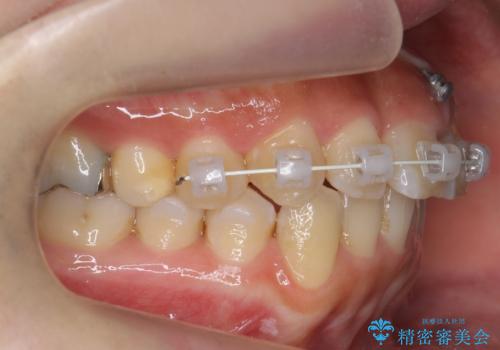

上の前歯をひっぱりあげて目立たなくするために、上の前歯のワイヤー部分矯正を行い、ミニスクリューからわずかに引っ張り上げました。

また、右上の犬歯の反対咬合についてもワイヤー矯正で短期間で改善することができました。

前歯(犬歯)の反対咬合は改善はインビザラインですと時間がかかるため、ワイヤー矯正で短期間で入れ替えるほうが、患者様の負担が少なくて済みます。

入れ替える期間は前歯しか当たらない状態になり、大変食事もしにくくなるうえ、前歯にも負担がかかります。ワイヤーは少々目立ちますがおすすめです。